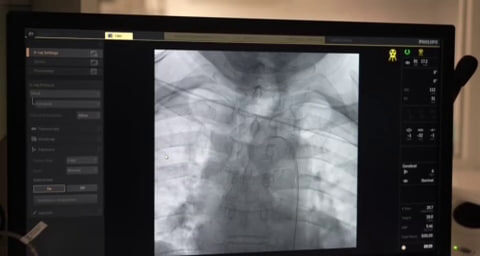

Мужчина обратился в волгоградскую больницу на консультацию после перенесенного инсульта. Медики обнаружили у пациента бляшку и решили провести операцию. Фото: облздрав В Волгограде медики предотвратили появление второго инсульта у мужчины. Пациента спасли врачи больницы №25. 69-летний мужчина обратился в больницу для консультации после перенесенного инсульта. При плановом обследовании у пациента нашли бляшку во внутренней сонной артерии. Она перекрывала просвет сосуда и могла привести к еще одному инсульту. Как сообщил заведующий отделением РХМДиЛ Андрей Легкий, симптомов у мужчины не было. Врачи решили установить стент для того, чтобы улучшить кровоток и не допустить повторного инсульта. В облздраве уточнили, что сейчас мужчина чувствует себя хорошо и готовится к выписке. Смотрим «Вести. Волгоград»: smotrim.ru/Volgograd Подписывайтесь на наши страницы в соцсетях: Telegram, ВКонтакте, Одноклассники, Дзен

Фото: облздрав

69-летний мужчина обратился в больницу для консультации после перенесенного инсульта. При плановом обследовании у пациента нашли бляшку во внутренней сонной артерии. Она перекрывала просвет сосуда и могла привести к еще одному инсульту.

Как сообщил заведующий отделением РХМДиЛ Андрей Легкий, симптомов у мужчины не было. Врачи решили установить стент для того, чтобы улучшить кровоток и не допустить повторного инсульта.